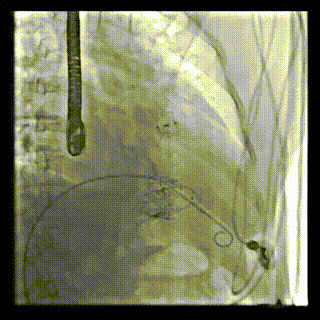

2021年12月24日,復(fù)旦大學(xué)附屬中山醫(yī)院葛均波院士團(tuán)隊(duì)成功應(yīng)用LuX-Valve Plus為一例極重度三尖瓣反流(TR)合并房顫、房缺的患者完成了經(jīng)血管三尖瓣置換術(shù),這是在前基礎(chǔ)上,本周完成的第三例經(jīng)血管三尖瓣置換手術(shù),葛均波院士、周達(dá)新教授等與心外科魏來教授、賴顥教授,心超室的潘翠珍教授、李偉教授及麻醉科的郭克芳教授共同完成了本周手術(shù),均獲得圓滿成功!患者術(shù)后超聲顯示無TR,臨床癥狀明顯改善。本周手術(shù)的成功也為LuX-Valve Plus救治性臨床研究添上了濃墨重彩的一筆。

本周三例接受LuX-Valve Plus經(jīng)血管三尖瓣置換術(shù)的患者中,第一例患者為冠狀動脈旁路移植術(shù)+Bentall+二尖瓣成形術(shù)后;第二例患者為永久起搏器植入術(shù)后,存在跨三尖瓣導(dǎo)線;第三例患者合并房顫、房缺及左心耳封堵術(shù)后。

三例患者入院后,葛均波院士團(tuán)隊(duì)周達(dá)新教授、潘文志教授、張?jiān)床┦?、陳莎莎博士及心超室的潘翠珍教授、李偉教授對患者的情況進(jìn)行詳細(xì)評估和討論,最終決定為三例患者選擇LuX-Valve Plus40mm、50mm和50mm型號的瓣膜進(jìn)行手術(shù)治療。手術(shù)后即刻拔除氣管插管,術(shù)后患者三尖瓣反流癥狀得到顯著改善,復(fù)查心超結(jié)果顯示人工三尖瓣瓣膜支架固定穩(wěn)定,瓣葉關(guān)閉形態(tài)未見異常,未見明顯反流。